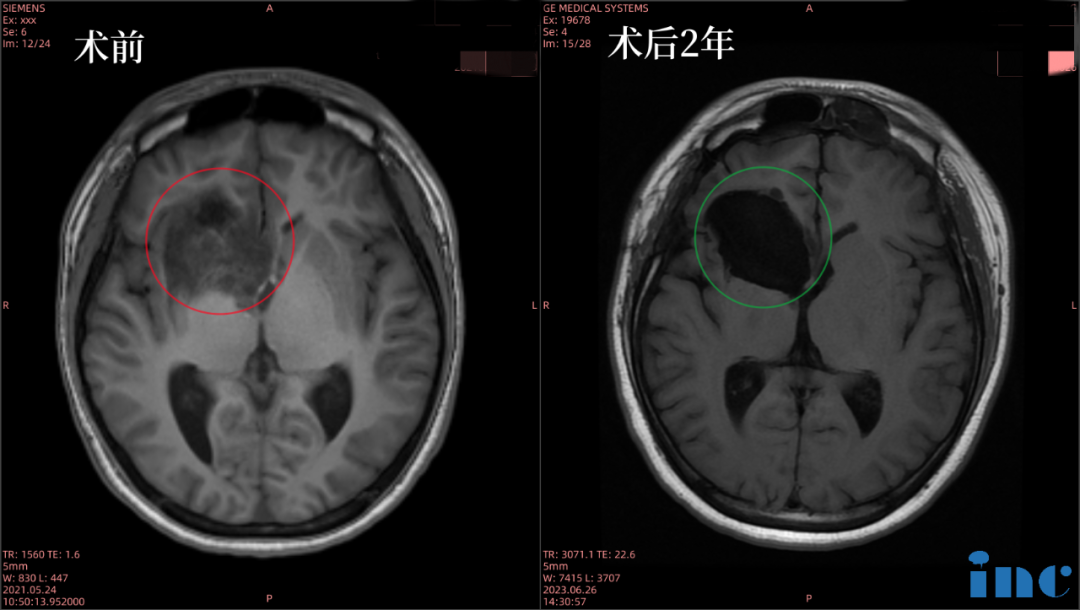

实例1:16岁男孩--右侧额叶、岛叶胶质瘤

16岁的小磊,被诊断出“右侧额叶、岛叶低级别神经胶质瘤,浸润基底节和侧脑室”。肿瘤位置比较深,并已经浸润到基底节,基底节区属于大脑功能区,手术风险较大。而且医生说很可能是低级别胶质瘤、进展慢,所以建议保守观察一段时间。但小磊父母怕拖得久了肿瘤会恶化,果断找到了INC。远程咨询时,和很多病友一样,他们关心:“这是胶质瘤吗?可能是哪个级别?恶性还是良性?”巴教授又是如何回复?

巴教授评估回复

“该病变看上去确实是胶质瘤,但并不是一种常见的病变,而是较少见的病变。关于是否是恶性肿瘤,我们不能从磁共振影像上确定,但我认为不是高度恶性的肿瘤,而是较低级别的病变。而手术的目的就是缩小多数的肿瘤的体积,并获得明确的组织病理结果。“